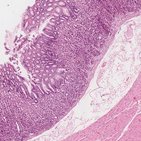

Agora me permita apresentá-lo à bela lâmina que nós vamos usar nesta videoaula. Eu tenho certeza que você vai notar imediatamente que a coloração usada aqui é hematoxilina e eosina, mais comumente conhecida como HE.

A hematoxilina é a tintura básica que cora estruturas acídicas, então coisas como os núcleos, que contém muito DNA acídico coram em azul escuro. A eosina é ácida, então ela se liga às estruturas básicas, como o citoplasma celular, que ela cora em vários tons de rosa.

Agora o que nós estamos vendo aqui pode ser inicialmente difícil de se identificar como duodeno, mas o que você pode ver agora na verdade é uma secção de uma biópsia retirada de uma das pregas circulares que nós vimos anteriormente, portanto você não será capaz de ver todas as camadas do duodeno nessa lâmina.

Agora vamos continuar e ver as camadas do duodeno. Vamos começar identificando todas as camadas do duodeno nessa imagem aqui. A primeira e mais interna camada é conhecida como mucosa, seguida pela submucosa, o revestimento muscular ou túnica muscular e a camada mais externa, chamada de serosa.

Então se você comparar a ilustração à lâmina histológica você será capaz de perceber que as camadas que nós estamos vendo são a mucosa e só um pequeno pedaço de submucosa. E agora nós podemos continuar para a nossa lâmina histológica. Primeiro nós estamos vendo a camada mais interna do duodeno a partir do lúmen - a mucosa.

Ela consiste em três camadas - a camada epitelial, a lâmina própria e a muscular da mucosa. A primeira coisa que nós podemos perceber na mucosa são essas estruturas alongadas se estendendo do duodeno até o espaço luminal. Cada uma dessas é conhecida como vilosidade intestinal. Elas servem ao mesmo propósito das pregas circulares - aumentar a área da superfície luminal do duodeno e maximizar a absorção.